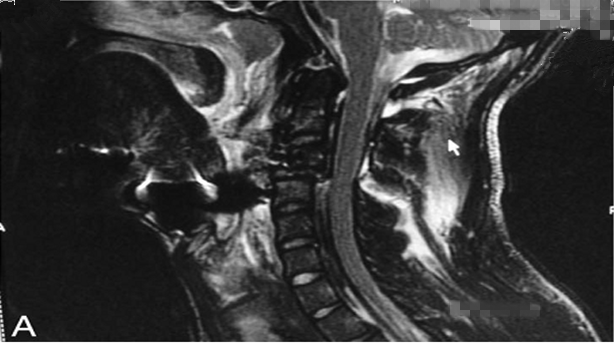

封面图